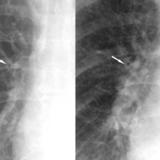

peribronchial cuffing

peribronchial cuffing bef and after

Date: 01/06/2018

Views: 6998